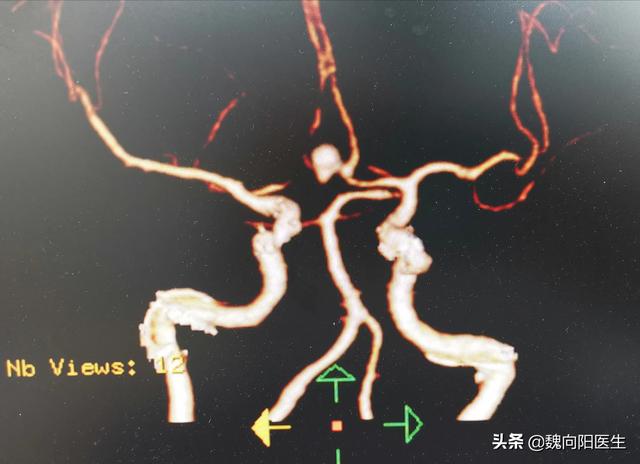

● 脳血管奇形の予防と治療:さまざまな脳血管奇形は、できるだけ早期に手術で治療し、原因を除去して脳出血の発生を防ぐ必要がある。

脳出血の原因は主に脳血管の病変と硬化に関係する。血管の病変は高脂血症、糖尿病、高血圧、血管の老化と密接な関係がある。血管狭窄は確かに高血圧を引き起こし、特に腹部大動脈、腎動脈狭窄や大動脈炎が二次性高血圧によって引き起こされる場合、脂質代謝異常は高脂血症を引き起こし、血管壁に脂質が沈着し、アテローム性動脈硬化症の形成を促進し、プラークの形成が増加し、徐々に血管をブロックするため、心血管疾患を引き起こし、脳で発生した脳卒中になります。同じことが血管の老化にも当てはまります。

- 脳アミロイドーシス、スモッグ病、動脈瘤、脳腫瘍など。

脳出血は重篤な脳血管障害であり、その原因は高血圧が最も多く、次いで血管奇形、外傷性脳損傷によるものもある!